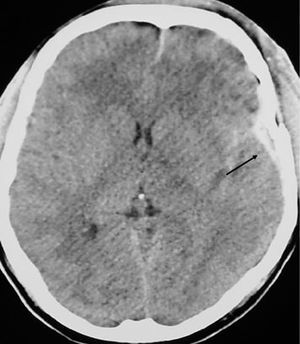

Presentamos el caso de un hombre de 24 años, que sufrió un traumatismo craneoencefálico (TCE), ingresando en una Unidad de Cuidados Intensivos (UCI) con un Glasgow Coma Score de 7 puntos. La tomografía axial computarizada (TAC) craneal mostró un hematoma extraaxial temporal izquierdo no subsidiario de cirugía (fig. 1). A continuación se realizó un dúplex transcraneal con codificación de color (DTCC) que confirmó la presencia de dicho hematoma, mostrando un tamaño de 45 x 9 mm (fig. 2). El hematoma extraaxial se pudo seguir en las siguientes 96 horas mediante DTCC a pie de cama sin apreciarse cambios en su tamaño. Se realizó entonces nueva TAC craneal que corroboró los hallazgos del DTCC. Posteriormente se pudo retirar sedación y extubar, encontrándose el paciente al alta consciente y sin focalidad neurológica.

Figura 1.